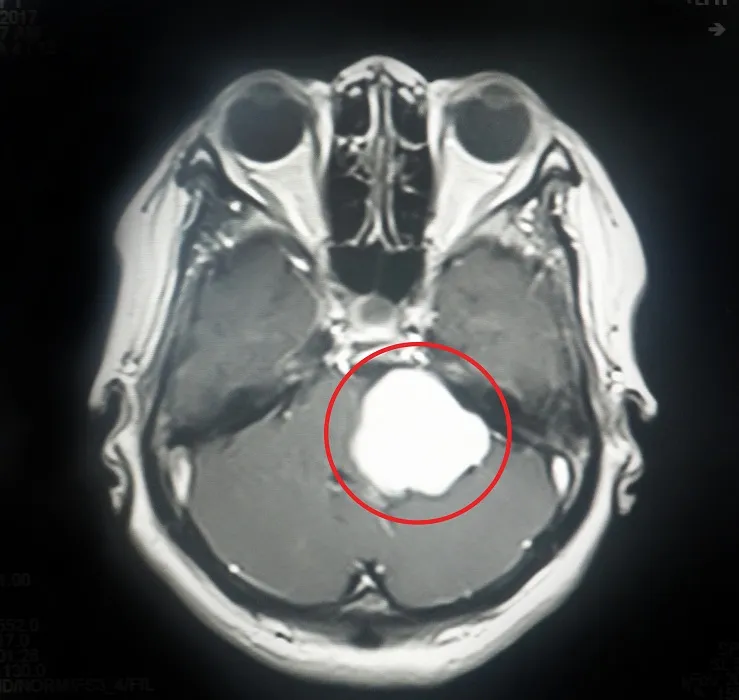

Qua thăm khám và kết quả kiểm tra lâm sàng, các bác sĩ xác định bệnh nhân có khối u não nằm rất sâu, ở vị trí liên quan tới nhiều dây thần kinh sọ não, và vùng chức năng quan trọng của não nơi điều hành nhịp tim và hô hấp.

Khối u màng não nằm ở vị trí khó

U màng não trở nên cực kỳ nguy hiểm, khó khăn khi điều trị nếu vị trí u nằm sâu, liên quan đến nhiều dây thần kinh sọ não và vùng thân não là vùng chức năng quan trọng của não như khả năng hô hấp, nuốt, nói...